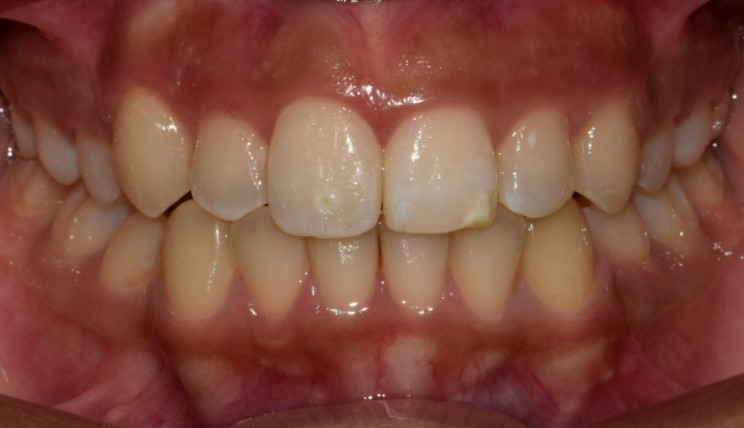

Crowding

Crowding is the condition in which there is a discrepancy between tooth size and space available for the teeth to be aligned in the dental arch

Patient Information:

Age: 17

Gender: female

Invisalign Treatment Option: Invisalign Comprehensive

Total Treatment Time:

29 months